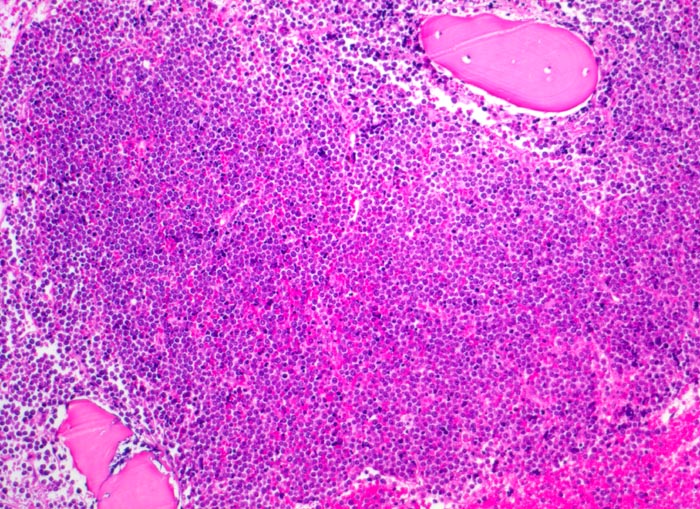

• Partielle Verdrängung des Fettmarks durch monomorphen Blastenrasen (Zellularität ca. 80%).

• Verdrängung der Myelo-, Erythro- und Megakaryopoese.

• Mittelgrosse Lymphoblasten mit wenig Zytoplasma.

• Kerne mässig polymorph, oval, teils mit Kerneinkerbungen. Feine Nukleolen. Lockeres Chromatin.

• Zahlreiche Mitosen.